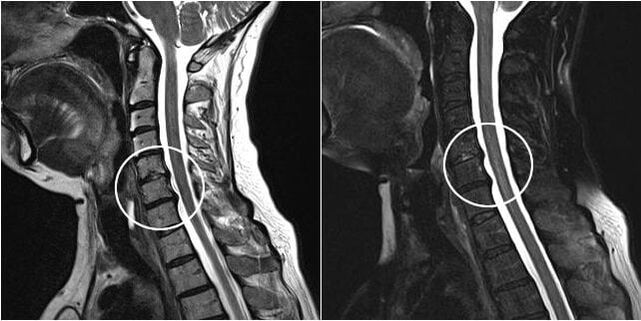

When the intervertebral discs and spine are deformed, the patient's condition worsens.The course of osteochondrosis is complicated by neurogenic symptoms caused by compression by osteophytes or herniated growth of spinal roots and vertebral artery.Headache, dizziness, changes in blood pressure appear, visual and hearing acuity decreases.

surgical intervention

Indications for surgical intervention include ineffectiveness of conservative treatment, as well as complications of cervical osteochondrosis, for example, discogenic myelopathy, vertebral artery syndrome, and radicular syndrome.The following operations are performed to decompress the spinal cord, blood vessels and spinal roots:

During the operation, it is possible to excision of bone fragments and ligaments and complete or partial removal of intervertebral discs.For small herniated disc herniations, laser ablation of the disc nucleus is often performed.